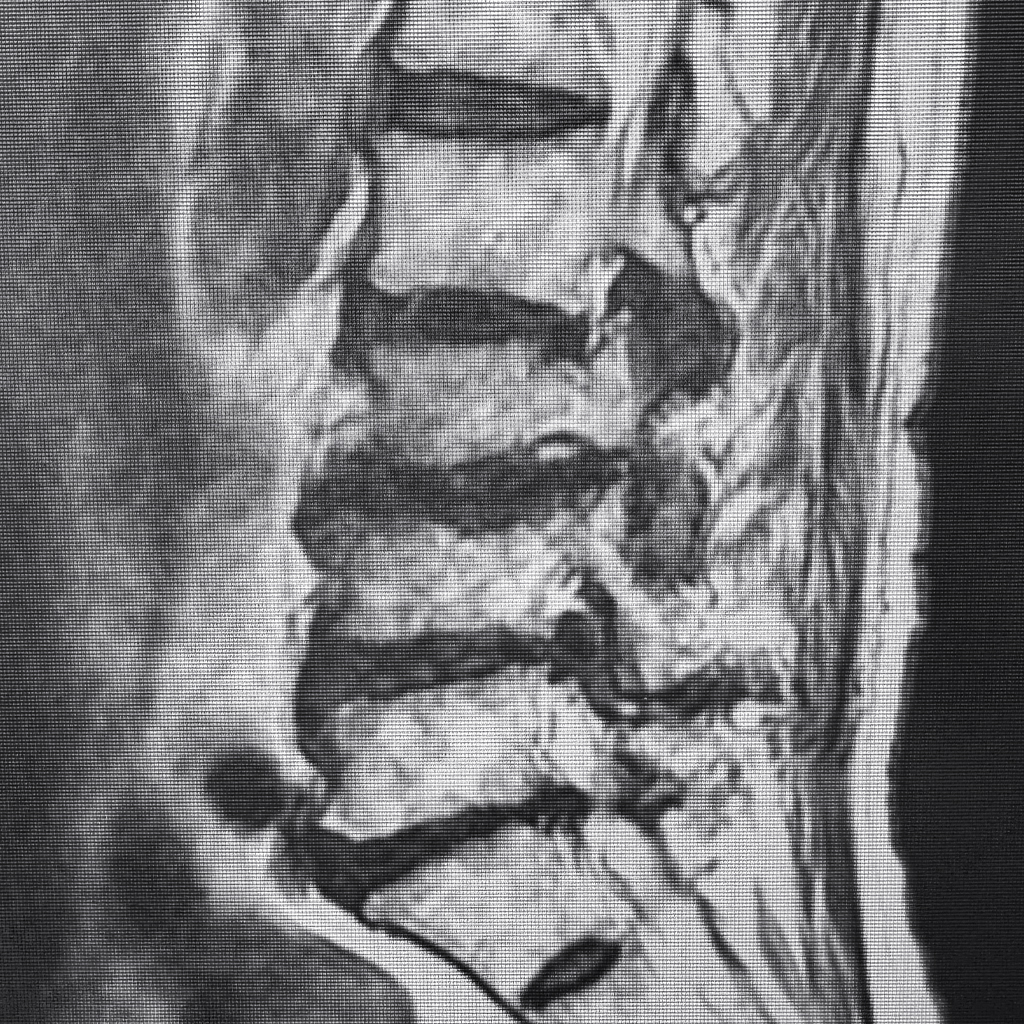

1年前のMRI検査結果ですが、椎間板容量は50%以上低下しており脊柱管狭窄症の合併も明らかです。